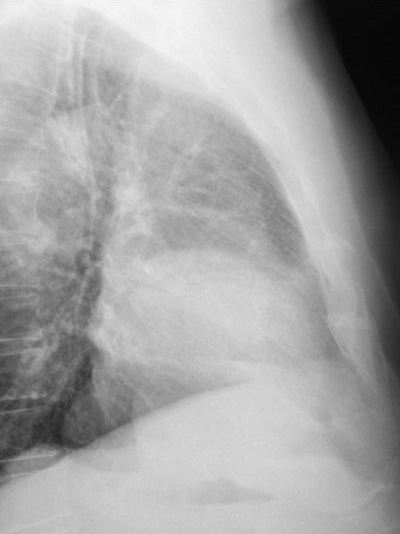

Atelectasia lóbulo medio.